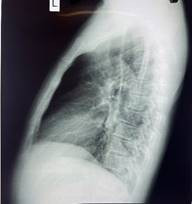

Hình: Viêm phổi tại phân thùy S6 phải - Ảnh BVCC

Bệnh nhân V.N.L (64 tuổi), trú tại xã Thới Lai, thành phố Cần Thơ, nhập viện trong tình trạng sức khỏe suy yếu do ho khan dai dẳng, thỉnh thoảng khạc đàm đục và sốt nhẹ kéo dài suốt nhiều tháng. Dù đã điều trị ngoại trú tại nhiều cơ sở y tế nhưng tình trạng bệnh không thuyên giảm, khiến chất lượng cuộc sống của bệnh nhân bị ảnh hưởng nghiêm trọng.

Qua thăm khám chuyên sâu và các kỹ thuật chẩn đoán hình ảnh, các bác sĩ Bệnh viện Lao và Bệnh Phổi Cần Thơ đã phát hiện dị vật mắc kẹt trong đường thở là nguyên nhân chính gây ra các triệu chứng trên. Ngay lập tức, ê-kíp can thiệp nội soi phế quản được kích hoạt khẩn cấp.